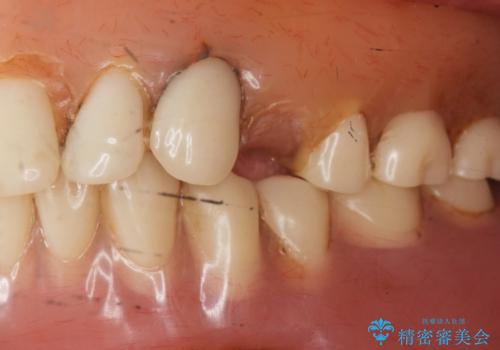

古い入れ歯は人工歯がすり減っており左右均等に咬むことができなかったそうですが、新しい入れ歯だと両側でしっかり咬むことができるとご満足頂けました。